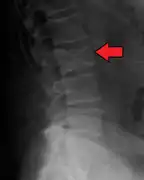

The diagnostic examination of a person with suspected multiple myeloma typically includes a skeletal survey. This is a series of X-rays of the skull, axial skeleton, and proximal long bones. Myeloma activity sometimes appears as "lytic lesions" (with local disappearance of normal bone due to resorption) or as "punched-out lesions" on the skull X-ray ("raindrop skull"). Lesions may also be sclerotic, which is seen as radiodense.[70] Overall, the radiodensity of myeloma is between −30 and 120 Hounsfield units (HU).[71] Magnetic resonance imaging is more sensitive than simple X-rays in the detection of lytic lesions, and may supersede a skeletal survey, especially when vertebral disease is suspected. Occasionally, a CT scan is performed to measure the size of soft-tissue plasmacytomas. Bone scans are typically not of any additional value in the workup of people with myeloma (no new bone formation; lytic lesions not well visualized on bone scan).

Pathological fracture of the lumbar spine due to multiple myeloma